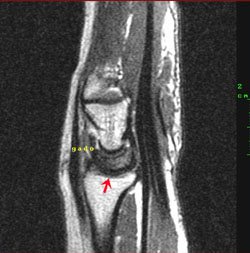

B - Coupe sagittale T1 Gadolinium : Prise de contraste relative au niveau de la corne antérieure du semi-lunaire.

D - Coupe coronale T1 : Hyposignal relatif du semi-lunaire prédominant au niveau de la surface sous chondrale proximale et sur le versant scaphoidien du semi lunaire, persistant y compris après injection de Gadolinium. Il semble qu'on retrouve également un certain degré d'aplatissement du pole proximal du semi lunaire sur son versant radial.